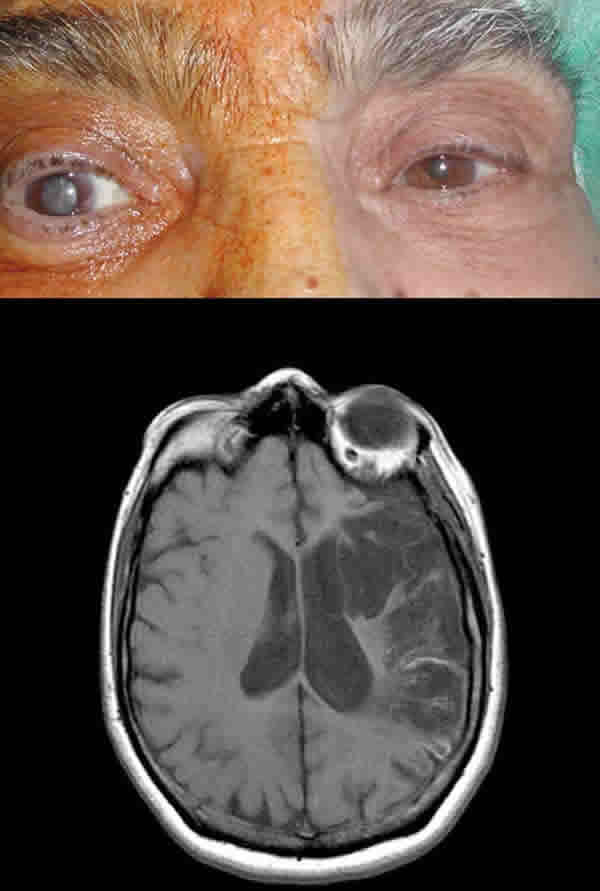

DPAR en la catarata

Desde hace tiempo se sabe que una catarata madura puede producir un defecto pupilar contralateral. La razón por la cual una opacidad de medios se comporta de un modo tan paradójico se desconoce. La serie más larga publicada examinaba cuarenta pacientes con cataratas asimétricas. En 23 pacientes aparecía un DPAR contralateral, que desaparecía o se invertía tras operar la catarata. En este estudio los autores no eran capaces de definir un tipo concreto de opacidad que se asociara con la aparición del defecto. Es posible que la catarata favorezca la dispersión de la luz que de este modo estimula una mayor superficie efectiva de retina o bien que se produzcan cambios compensatorios en la sensibilidad retiniana. En cualquier caso, se trata de un DPAR de bajo grado (a lo sumo de 0,3 unidades logarítimicas) (15,16) (fig. 6).

Fig. 6: Dos situaciones pueden justificar la aparición de un DPAR contralateral: la catarata cuando es muy asimétrica (imagen superior), y una lesión de la cintilla óptica (imagen inferior). La irrigación de la cintilla depende de la arteria cerebral media, por lo que debe tratarse de un infarto cerebral extenso, como el que aparece en esta imagen.

DPAR en las lesiones de cintilla

En las lesiones del tracto óptico, cuando éstas son muy extensas es posible demostrar la presencia de un DPAR de muy bajo grado, contralateral al lado de la lesión. La explicación clásica de que la retina nasal se extiende más que la retina temporal, y de que por lo tanto la cintilla porta más fibras procedentes del ojo contralateral que del ojo ipsilateral, parece algo inocente, pues la asimetría es tan pequeña que no justifica por sí sola la aparición del defecto. Es más probable que el defecto se deba a una mayor sensibilidad de la retina nasal que de la retina temporal (17) (fig. 6).